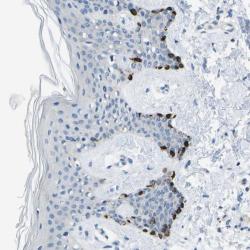

Supportive validation

- Experimental details

- Immunohistochemical staining of human skin shows strong cytoplasmic positivity in a subset of cells.

- Validation comment

- Two independent antibodies targeting one protein yielding similar staining patterns. Staining pattern consistent with experimental and/or bioinformatic data.